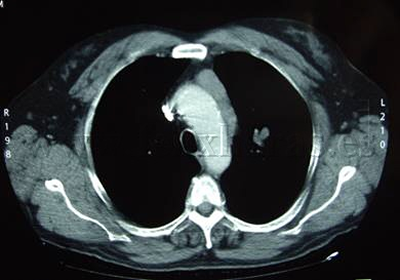

Cáncer de pulmón